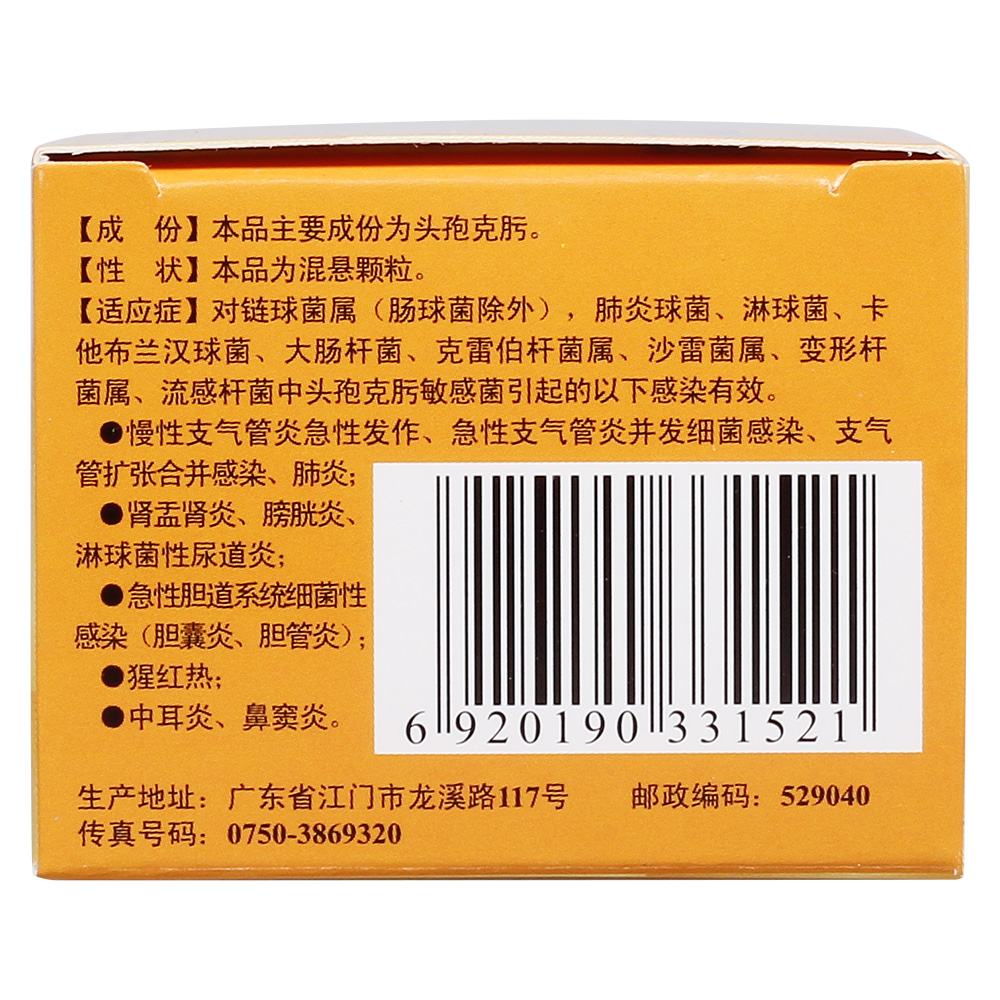

但是,别怕,我们不是孤军奋战。医生们都是我们的战友,他们有各种武器——抗生素、药物,还有先进的医疗设备,都在帮我们对抗这些顽固的敌人。